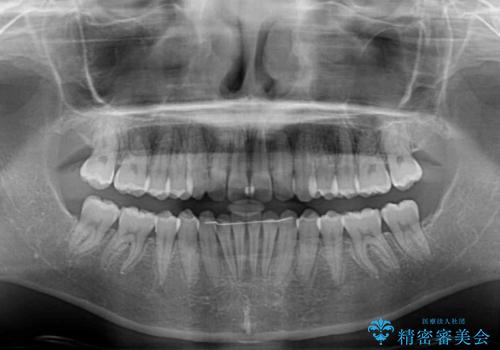

- 前歯のデコボコと下の前歯が隠れてしまう咬み合わせを気にして来院された患者様です。

インビザラインによる上下歯列の拡大と、IPR(歯と歯の間を削る)にるスペースの獲得により、口元のデコボコとディープバイトを改善することとしました。

インビザラインは、装着していない時間がどれだけ短いかが、治療期間を大きく左右します。こちらの患者様は1日22時間以上、毎日欠かさず装着してくださったため、1年弱という短期間で満足のいく歯列に整えることができました。